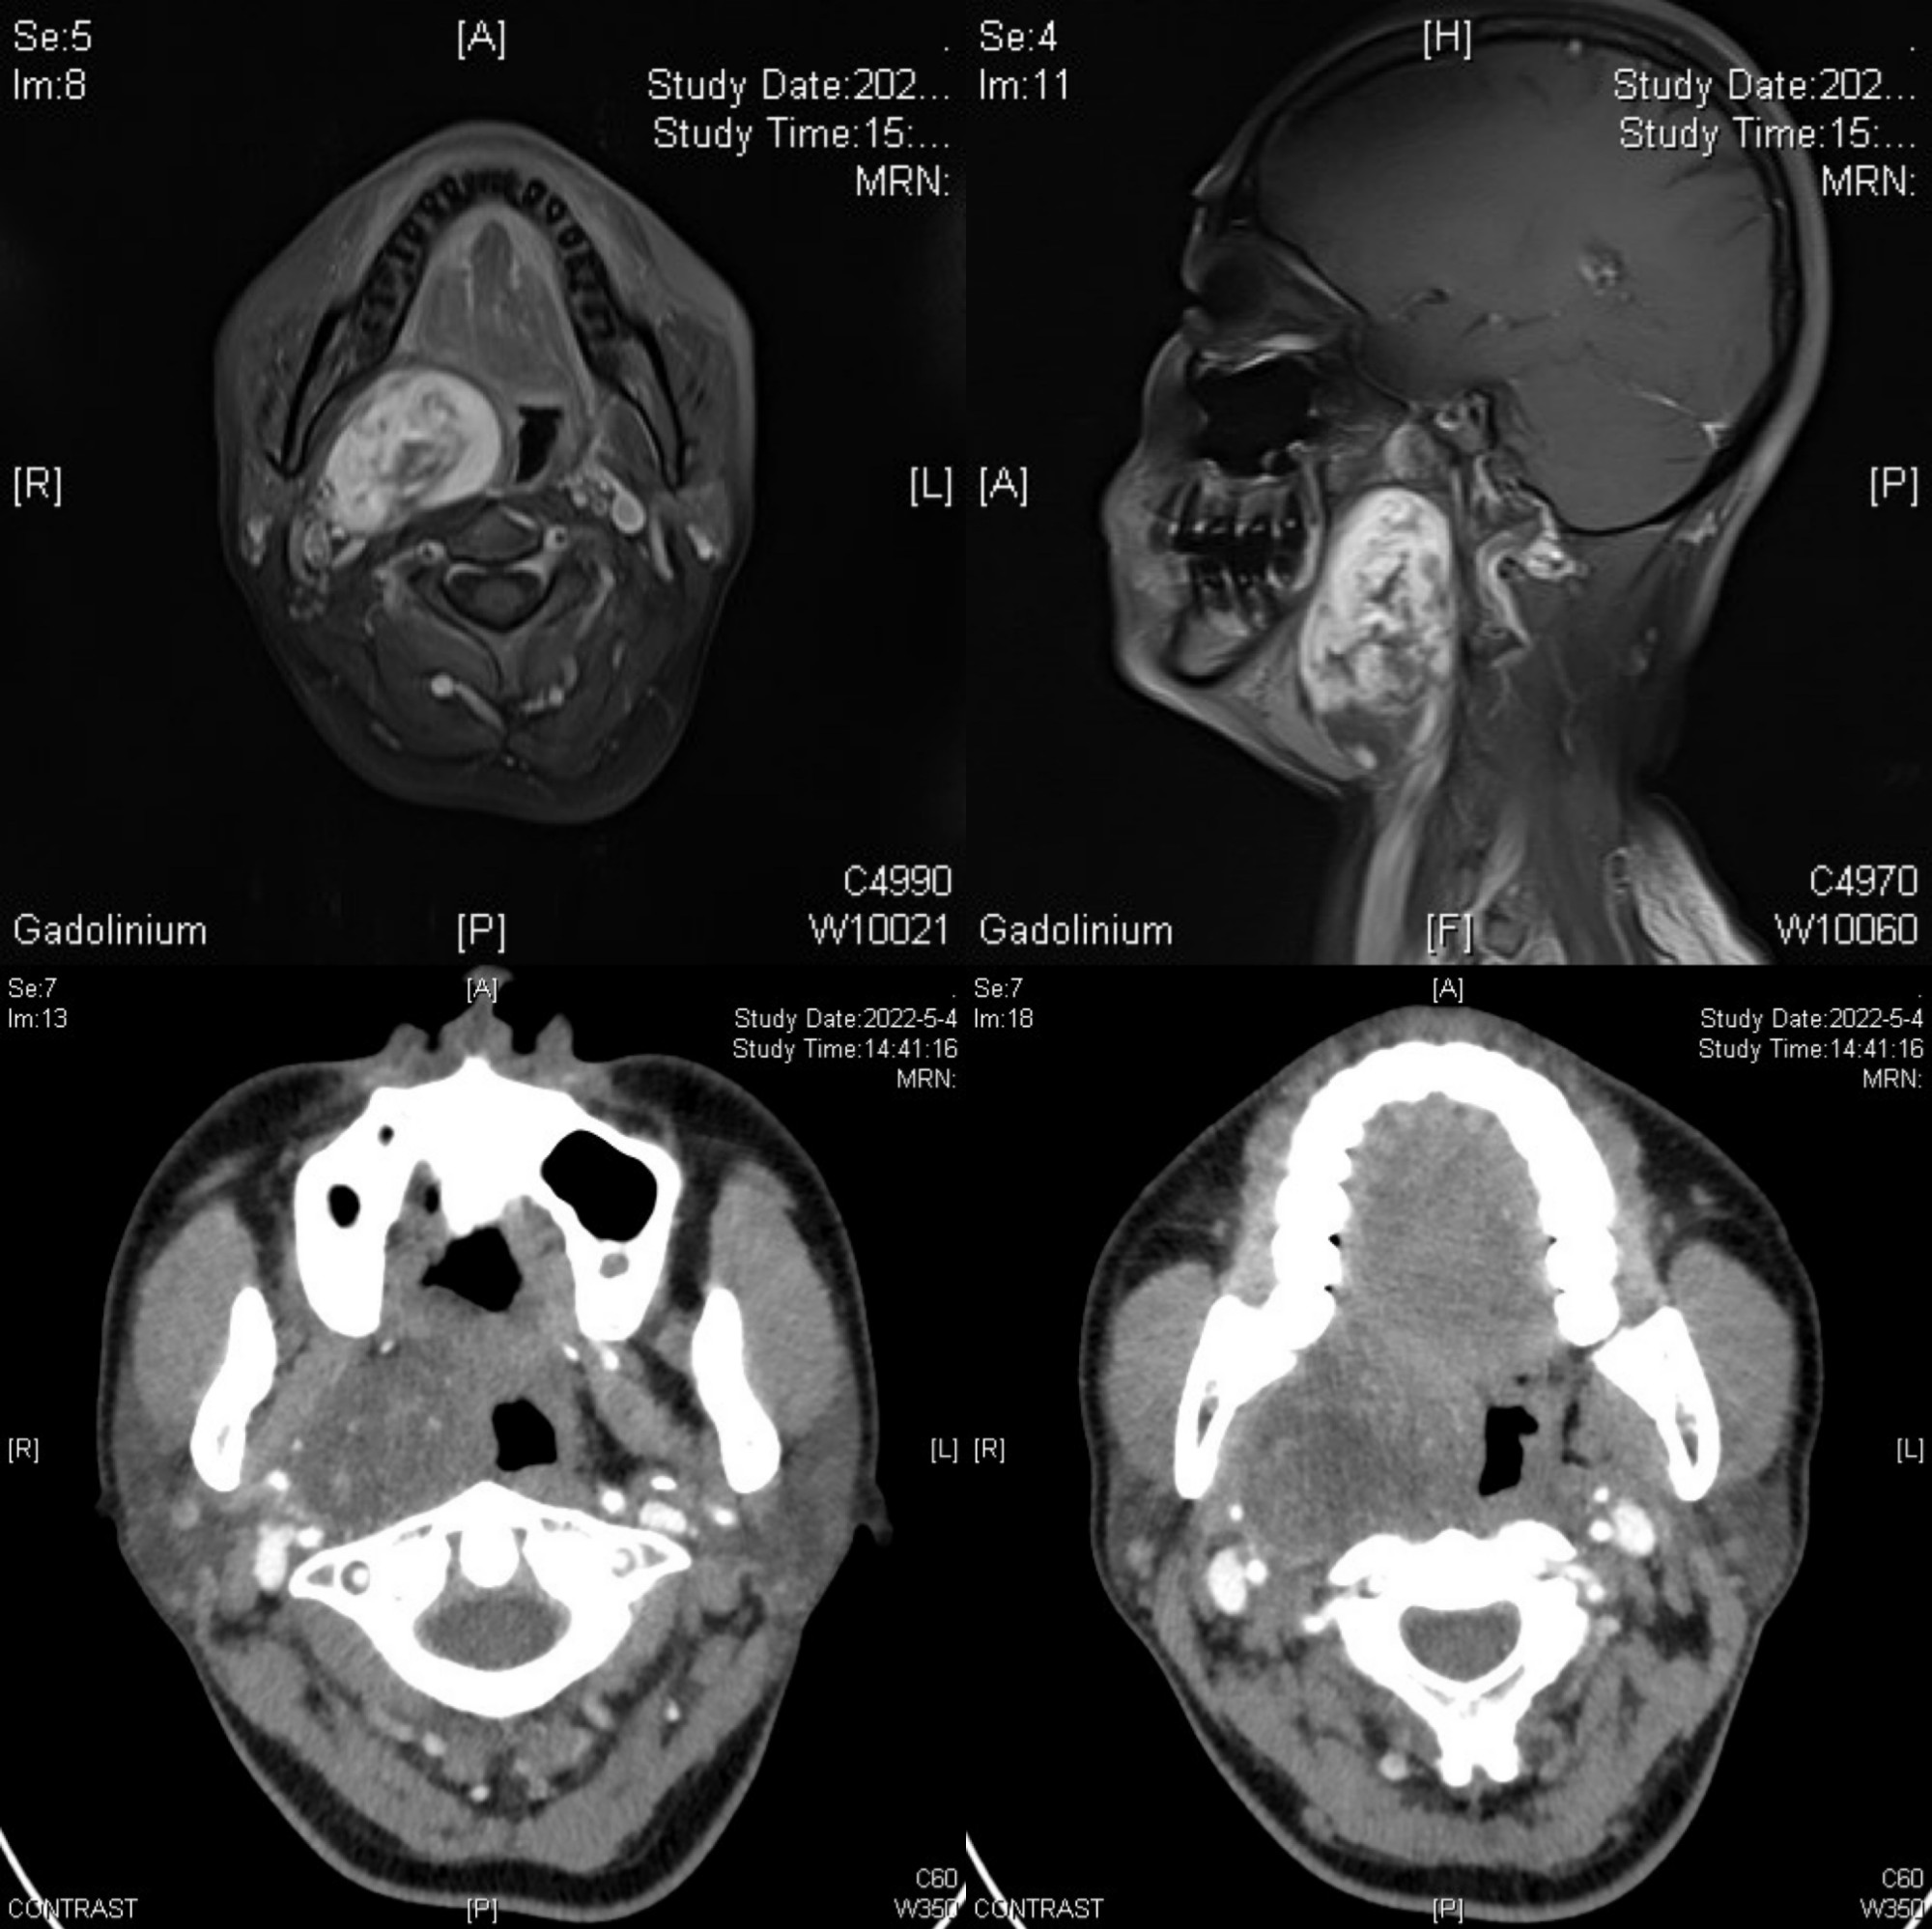

患者女性,47岁,因发现右颌下区肿物6年入住我院口腔颌面外科。入院后经过颌面部增强CT和增强MRI检查发现患者为右侧口咽部肿物,肿物体积较大,上达颅底翼外肌水平,下至甲状软骨水平,致使半侧咽腔堵塞。李家锋主任凭借影像学资料及多年的临床经验,初步考虑为神经鞘瘤可能。但由于肿物体积较大,位于咽侧深区,毗邻颈部重要大血管,致使该手术具有较大的难度和风险。既往对于该类型肿瘤,由于肿物体积较大,为避免重要血管及神经损伤,术中需暂时劈开下颌骨暴露肿物实施手术。术前和患者及其家属沟通后,患者对下颌骨暂时劈开心理负担很大,希望尽可能避免下颌骨的劈开。

为减少手术创伤及考虑到患者及其家属强烈要求,避免下颌骨暂时劈开,李家锋主任、吕中静博士在术前经过周密考虑并制定详尽的手术计划,带领团队成员通过颈外入路囊内摘除方式成功摘除肿瘤。术中发现该患者为来源于迷走神经的神经鞘瘤,李家锋主任、吕中静博士及团队成员在手术实施过程中,精准分离,充分保护颈内外动静脉及迷走神经,该患者术后并无相应的神经症状手术并发症的出现。该患者在术后1周顺利出院。该手术的成功实施,不仅最大程度减轻了患者的身体伤害,降低了患者经济负担,还加速了患者术后康复,缩短了术后康复时间。